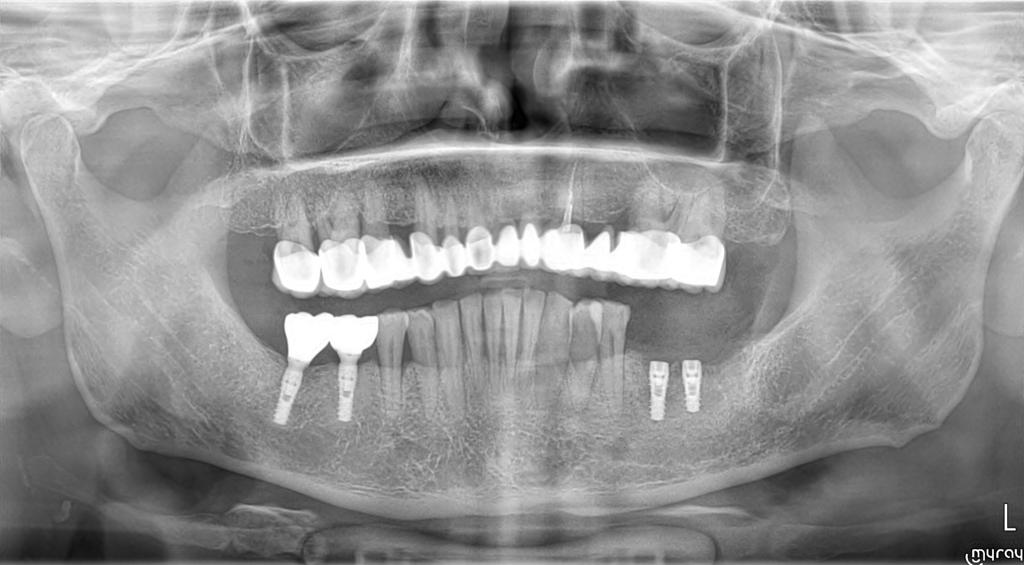

Case Presentation: A 42-year-old male patient with high diabetes and heavy smoking-alcohol use presented with multiple tooth loss. These systemic health factors posed potential risks for implant treatment. However, successful implant placement with Naxis implants was achieved in sites 46-47 to address the patient's dental needs. Approximately two years later, implants were also placed in sites 36-37 using Naxis implants.

Post-Treatment Evaluation: The patient continued smoking and alcohol consumption after implant surgery. However, evaluation of the long-term stability and success rates of the implants, based on X-ray images taken five years later, revealed that the Naxis implants were securely maintained. This demonstrates that successful implant treatment is possible despite the negative effects of systemic health factors, with regular follow-up and periodontal care.